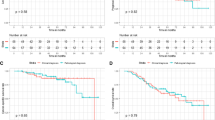

Fluorodeoxyglucose (FDG)-PET has been a useful tool for the evaluation of treatment response after conventional fractionated radiation therapy for NSCLC. It is unclear whether FDG-PET is equally useful in patients who received SABR for lung tumors. Data in the literature on the use of FDG-PET in the evaluation of post-SABR response are emerging [3]. One of the earliest studies includes a retrospective study from Indiana University, where 14% of patients treated with SABR for medically inoperable NSCLC in a prospective trial maintained a moderate standardized uptake value (SUV) (defined as higher than 2.5) 22–26 months after treatment and upon longer follow-up (42–49 months), remaining alive without evidence of disease recurrence [16]. In an Indiana University pilot trial of serial FDG-PET in patients with medically inoperable stage I non-small cell lung cancer treated with SABR, serial FDG-PET/CT was done before SBRT and at 2, 26, and 52 weeks after SABR. It was observed that patients with low pre-SBRT SUV were more likely to have an initial 2-week rise in SUV, and patients with high pre-SABR SUV frequently had a decline in SUV 2 weeks after treatment [17]. Six out of 13 patients had primary tumor maximum SUV of >3.5 at 12 months after SBRT but did without any evidence of local disease failure on subsequent follow-up. In a study from Kyoto University, Matsuo demonstrated that FDG uptake tended to be intense and well defined at early periods after SABR, especially within 6 months, and was faint and ill-defined at later periods. Moderate to intense FDG uptake on PET soon after SABR did not always represent a residual tumor [18]. Figures 3 and 4 showed the serial changes on FDG-PET after SABR.

Other studies have demonstrated good correlation between FDG-PET findings and response to treatment. Coon et al. found that after SABR for primary and recurrent NSCLC, and lung metastases, patients with stable disease, partial response, complete response, and progressive disease had a decrease in SUV of 28%, 48%, 94%, and 0.4%, respectively [19]. In a study by Fuss et al., 38 patients with stage I NSCLC were treated with SABR to doses ranging from 36 to 60 Gy in 3 fractions. Follow-up FDG-PET studies at an interval of 4–12 weeks were available in 30 patients. Changes in SUV were seen as early as 4 weeks, and there was a decrease of SUV to less than 3.0 in 28 patients at 12 weeks [20]. The remaining two patients without a decrease of SUV in the treated tumor developed local failure. Similar to the study by Fuss et al., Feigenberg et al. from Fox Chase Cancer Center found that a decrease of SUV on FDG-PET at 3 months after SABR strongly correlated with the local control in 18 patients treated for NSCLC. Sixty percent of patients with no decrease of SUV developed local failure 9 months to 1 year after post-SABR FDG-PET [21].

In an attempt to more accurately evaluate response of lung tumors to SABR, FDG-PET, which demonstrates tumor activity based on glucose uptake, has been used as follow-up imaging. In general, a decrease of SUV correlates with tumor response and local control [19–21]. However, some studies show that SUV may transiently increase shortly after SABR, presumably due to inflammatory reaction [16–18]. Furthermore, moderate increase in SUV can occur 2 years or more after treatment in patients without evidence of tumor recurrence [16].

For both CT and FDG-PET, the need for follow-up using serial imaging cannot be overemphasized. Based on observations from the literature, controversies still exist as to whether FDG-PET is superior to CT for the follow-up of patients who receive SABR for lung tumors. Currently, Radiation Therapy and Oncology Group protocols of SABR for medically inoperable early-stage NSCLC predominantly are using CT to monitor tumor response, and FDG-PET is only obtained to look for FDG avidity similar to the initial tumor presentation if tumor enlargement occurs.